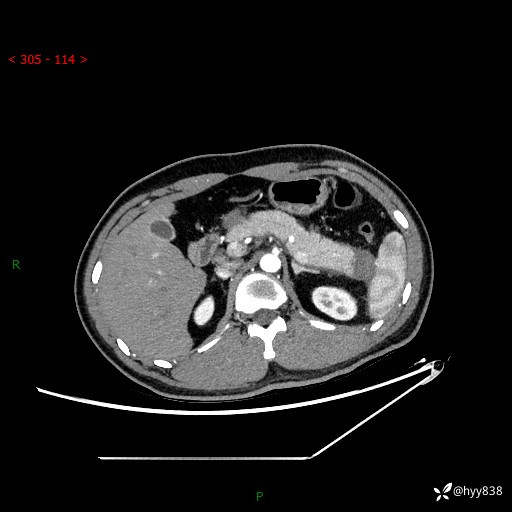

【患者信息】:31岁/男

【主诉】:间断性左下腹疼痛10天

【现病史及既往史】: 患者10余天前无明显诱因出现左下腹部疼痛,呈间断性,无恶心,呕吐,无黄疸,腹泻症状,于当地医院就诊,行腹部C提示:胰腺尾部占位。2型糖尿病。现患者为求手术治疗,门诊以“胰腺肿物”收入院。 患者起病来,一般情况可,大小便正常,体重体力未见明显减轻。

【检查】:胰腺CT平扫+增强